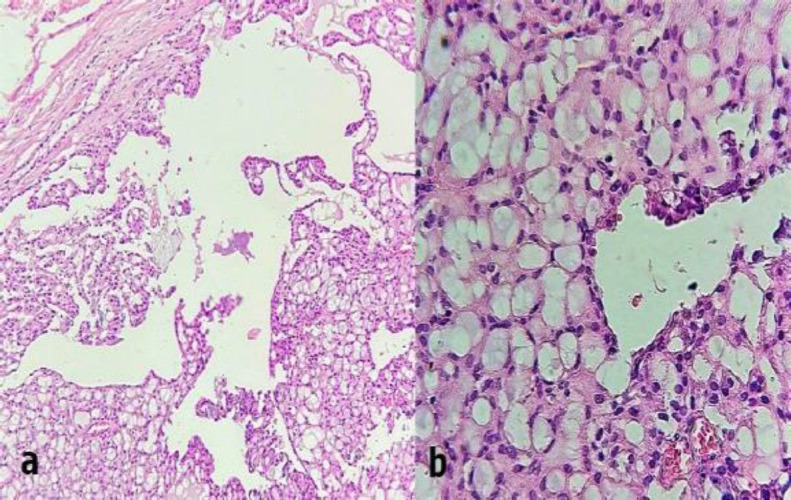

Case report: This report presents the case of a 32-year-old female patient with a painless swelling of the upper lip and a history of recent surgery for an immature ovarian teratoma. The microscopic sections revealed a circumscribed neoplasm composed of macrocystic, papillary-cystic, and microcystic patterns with bland vesicular nuclei and vacuolated cytoplasm. Tumoral cells were strongly positive for mammaglobin, SOX10, GATA3, S-100, and vimentin. The diagnosis of salivary gland secretory carcinoma was made. After 22 months, there has been no recurrence.